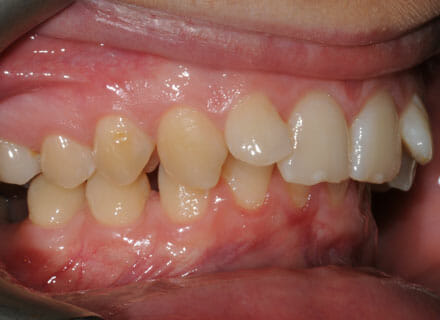

This lady came to us because she was unhappy with her crooked, uneven teeth.

The front ones were sticking out and she didn’t like her overbite. we were to move all the teeth sticking out back to where they should be, at the same time we made all the teeth nice and straight.

Treatment duration: about 12 months.

Brace Type: clear brackets